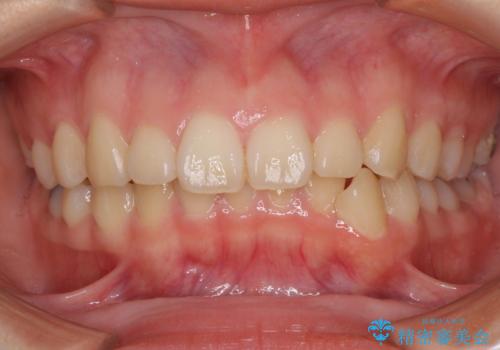

唇を閉じやすく 出っ歯の抜歯矯正

担当医 藤巻太一朗